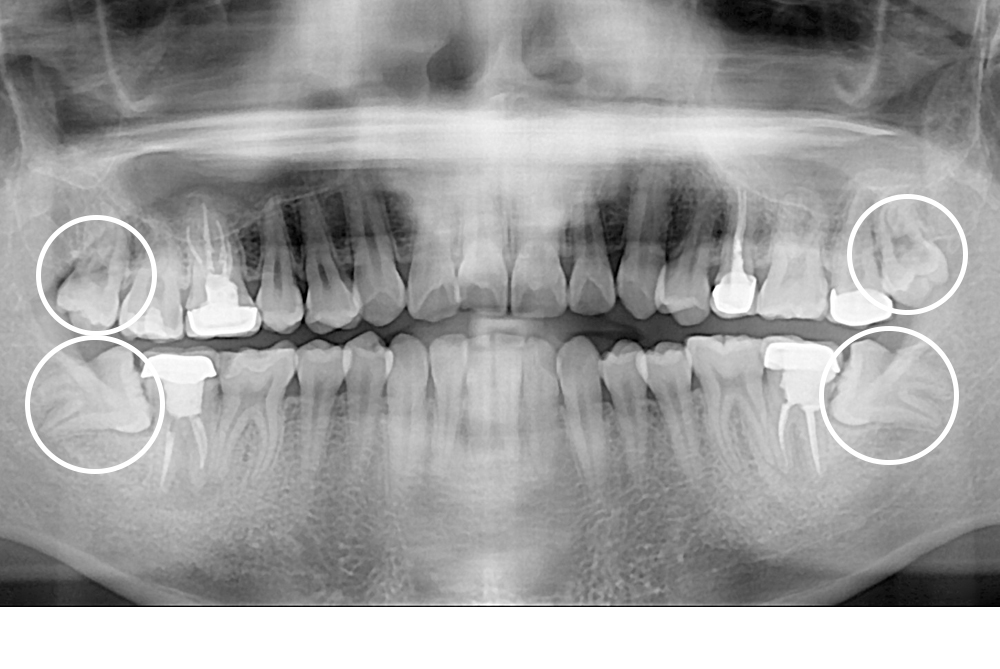

[사랑니] 매복 사랑니 발치

치료후 : 2020-06-19

세종치과는 구강악안면외과학 박사이신 원장님이 발치하는 치과입니다.